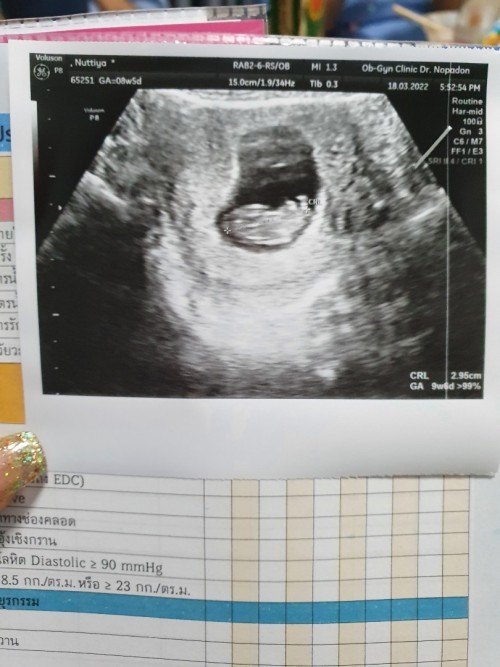

ซาวตอน 9/6 แต่วันนี้ 10 พอดี

Post reply image